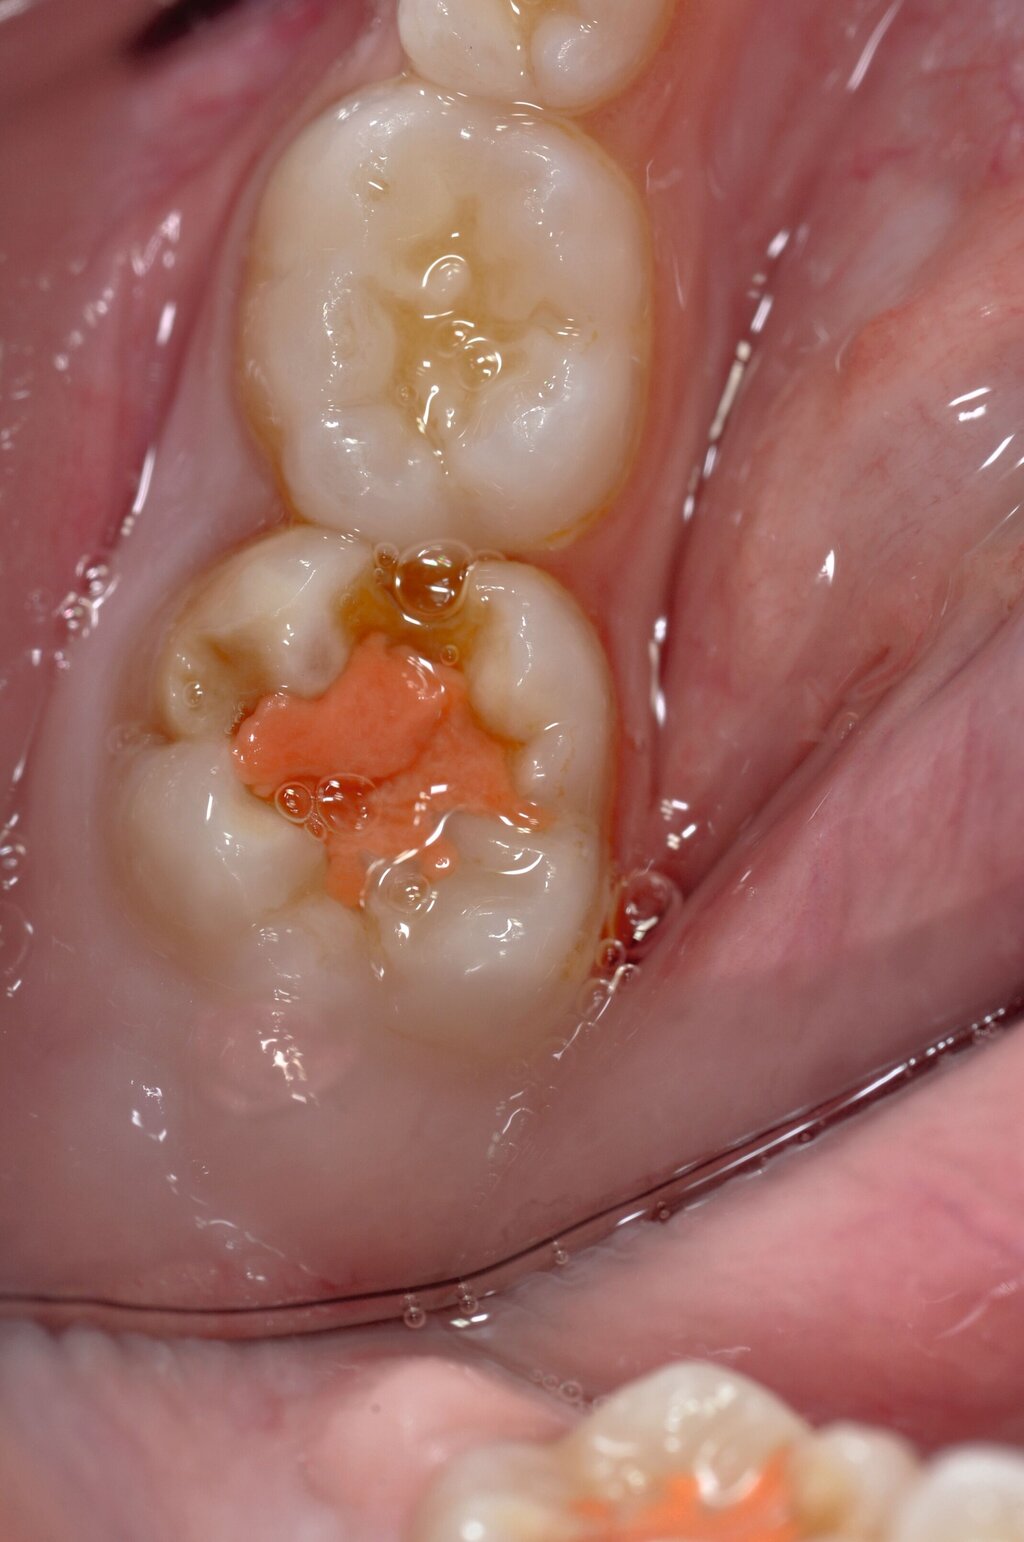

Die temporäre Therapie C (kurzfristig)

Die Therapie C hat das Ziel, MIH-Zähne vorübergehend zu versorgen, bis der vollständige Durchbruch der Zähne eine adhäsive Restauration ermöglicht, um die hypersensiblen Zähne zu desensibilisieren oder/und die Mitarbeit für die weitere Behandlung aufzubauen. Vor dem Hintergrund des erhöhten Kariesrisikos dieser Zähne (Abbildung 2) muss durch die Maßnahmen eine Kariesprogression vermieden werden.

Als mögliche Maßnahme steht eine Abdeckung der Defekte mittels konventioneller Glasionomerzemente (GIZ) zur Verfügung. Vorteil der Materialien ist die schnelle und einfache Applikation der Zemente. Bei MIH-Molaren werden diese in der Regel mittels der sogenannten ART-Technik (Atraumatic Restorative Treatment) eingesetzt [Grossi et al., 2018]. Dabei wird lediglich mit einem Handinstrument die Zahnoberfläche gereinigt und gegebenenfalls Karies exkaviert. Anschließend wird die Kavität unter relativer Trockenlegung mit dem GIZ aufgefüllt.

Der Vorteil der Methode ist, dass die betroffenen Zähne auch ohne Lokalanästhesie und Präparation versorgt werden können. Die temporäre Versorgung ermöglicht es, die Patienten an die zahnärztliche Behandlung zu gewöhnen. Häufig führt diese temporäre Versorgung auch zu einer Reduktion der Hypersensitivität der MIH-Zähne. Nachteil der GIZ-Versorgung ist das Risiko einer Füllungsfraktur oder eines vollständigen Verlusts der Füllung (Abbildung 4). Aktuelle Erhebungen bestätigen eine Erfolgsrate von über 80 Prozent nach einem bis zwei Jahren [Durmus et al., 2021; Mahfouz et al., 2025].

Der Behandlungsfall (Abbildung 4d) veranschaulicht die Schwächen des Verfahrens. Wird das Angebot der regelmäßigen Kontrollen nicht wahrgenommen, so droht bei Verlust der Füllung die Kariesprogression. In dem vorliegenden Fall konnte jedoch eine endodontische Maßnahme vermieden und durch die selektive Kariesentfernung die Zahnhartsubstanz weitestgehend erhalten werden.